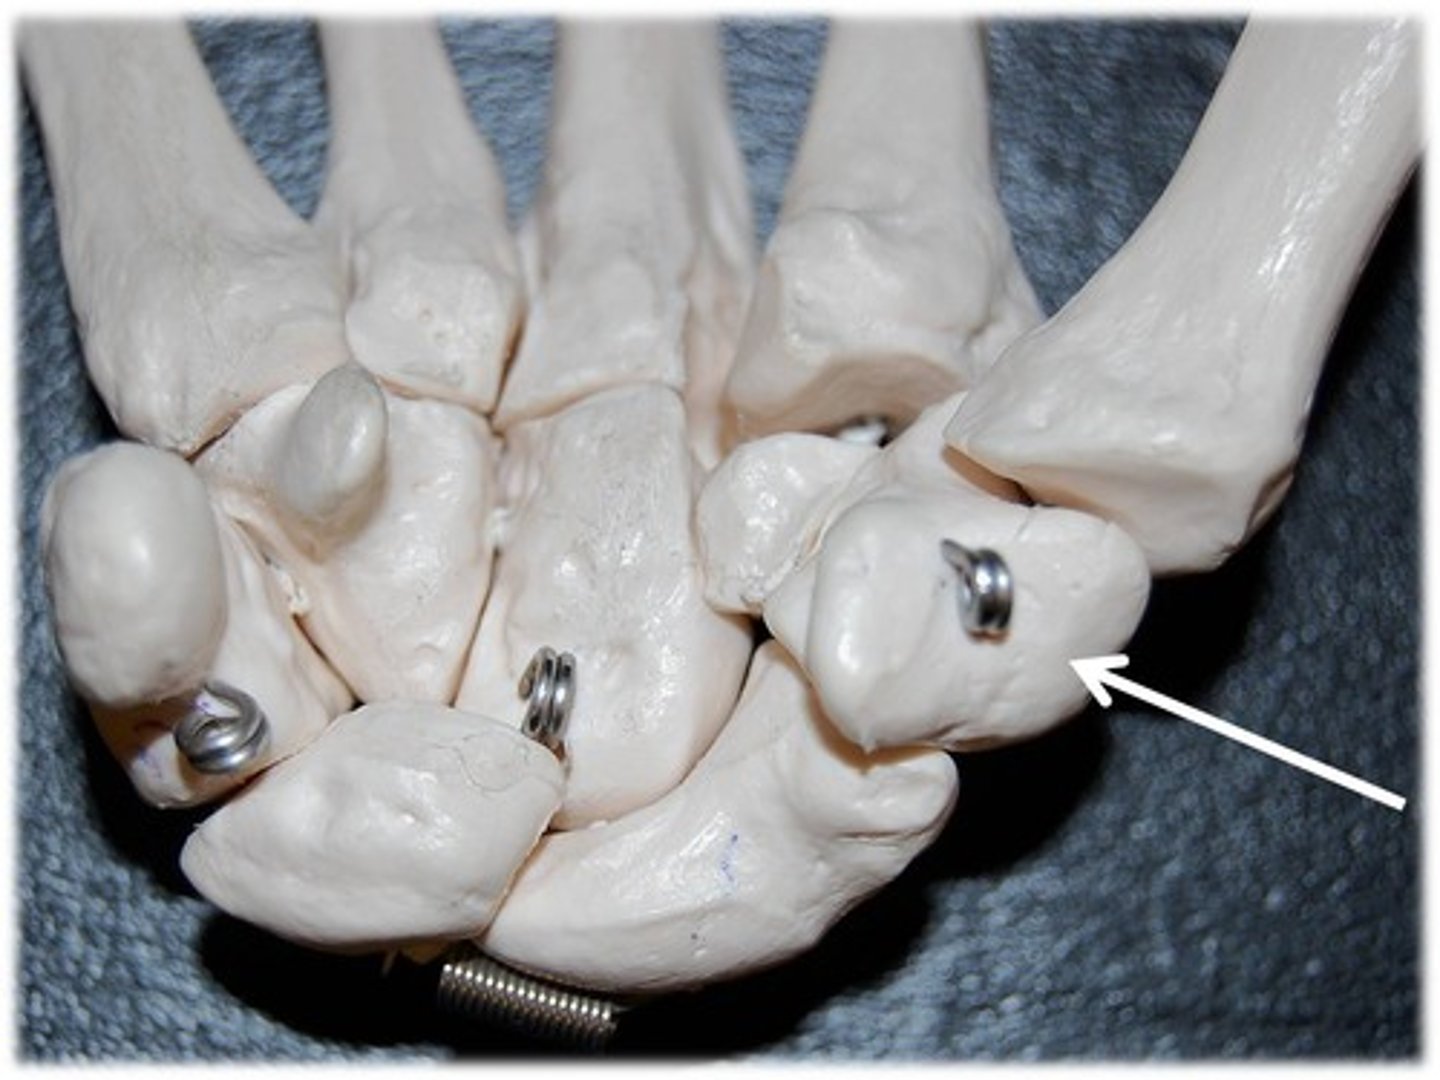

metacarpals

1st metacarpal

ID bone

1st proximal phalanx

ID bone

4th proximal phalanx

ID bone

4th metacarple

ID bone

carpals

ID group

hamate

ID bone

1st metacarple

ID bone

metacarpals

ID bone group

carpals

ID bone group

phalanges

ID bone group

metacarpal

ID YELLOW bones

carpals

ID PURPLE bones